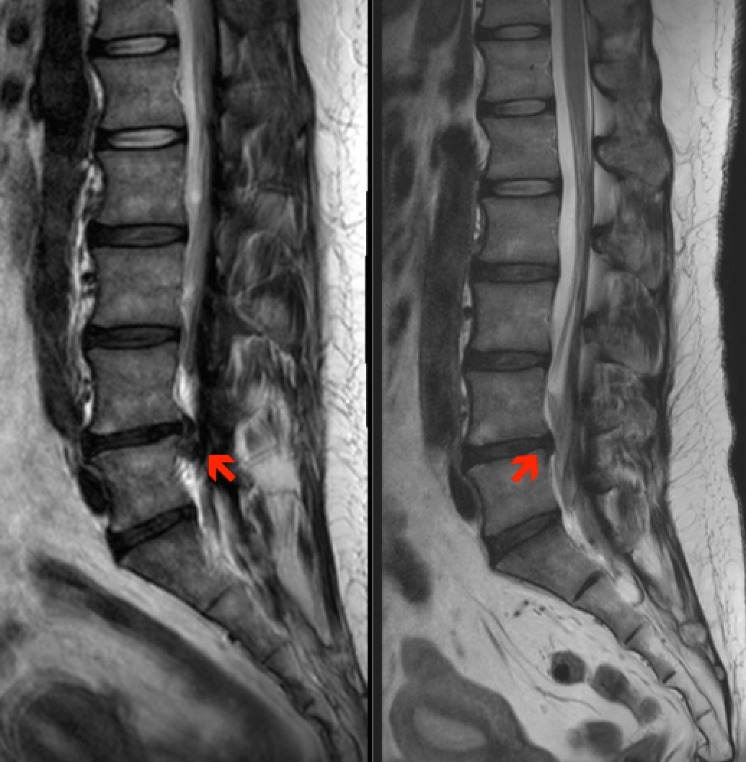

X小姐,年齡38歲,有下背痛及左下肢坐骨神經痛的症狀,無法正常行走,腰椎磁震照影檢查發現在腰椎第四/五節間的椎間盤有突出(圖左),復健及藥物治療無效,因為害怕手術,所以到疼痛科接受腰椎注射治療,一週後症狀明顯改善,可以回到工作崗位,1個月後已沒有疼痛,3個月的磁震照影可以看到大部份突出已經消失(圖右)。